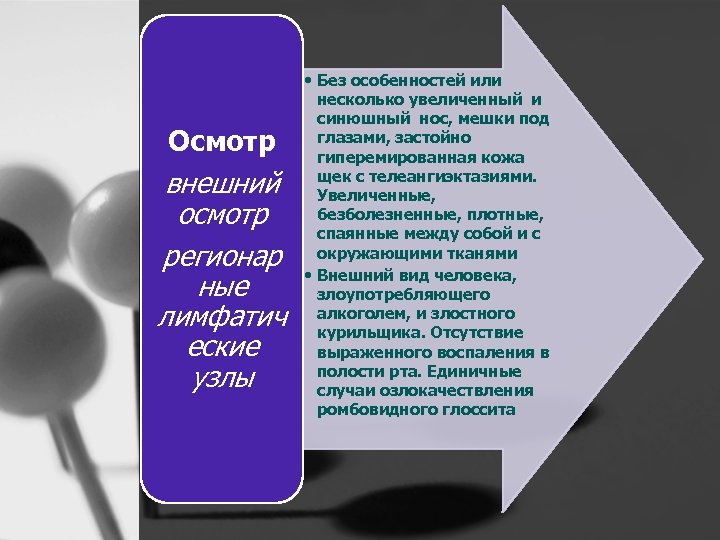

Осмотр внешний осмотр регионар ные лимфатич еские узлы • Без особенностей или несколько увеличенный и синюшный нос, мешки под глазами, застойно гиперемированная кожа щек с телеангиэктазиями. Увеличенные, безболезненные, плотные, спаянные между собой и с окружающими тканями • Внешний вид человека, злоупотребляющего алкоголем, и злостного курильщика. Отсутствие выраженного воспаления в полости рта. Единичные случаи озлокачествления ромбовидного глоссита